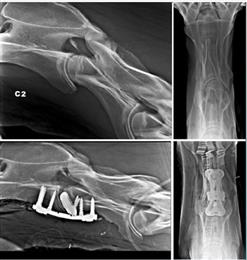

Neck fractures in horses can be successfully stabilized using a combination of conventionally manufactured compression screws, dorsal laminectomies or ventral cervical fusions, using "baskets" or threaded cylindrical cervical cages. Cervical arthrodesis – the fusion of two or more bones in a joint – can be performed on horses with neck fractures (or vertebral dislocation), instability or malalignment. Historically, surgery has been performed by placing locked plate implants (LCP).

During surgery, the injured horse is anesthetized and placed in a surgical hammock to immobilize it. The fracture is stabilized with a 3D-printed plate and 3D-printed cancellous screws bridging the vertebrae, and depending on the case (and the vertebrae affected) with a small 3D-printed titanium cage applied in the ventral disc space. Cancellous or cortical screws may sometimes be associated with the locked screws to allow compression of the fractured fragment.

The benefit of this assembly lies in the fact that the 3D-printed titanium intervertebral spacer used during surgery makes use of compression forces to preserve the spacing between the vertebrae, thus preventing the protrusion of the disc in the medullary canal and the ventral displacement of the caudal vertebra.

The shape of the plate allows the placement of three screws in each vertebra. In addition, implants manufactured using titanium alloys have shown better osseointegration than steel implants. And unlike conventional machining, metal 3D printing allows for the creation of porous patterns that facilitate the growth of bone through the cage and the fixation of the bone onto the cage.

The procedure is performed under radiographic or fluoroscopic control, and so far, few complications have been noted. The most common are the appearance of a seroma and the disinsertion of screws. Seromas generally respond very well to conservative treatment.